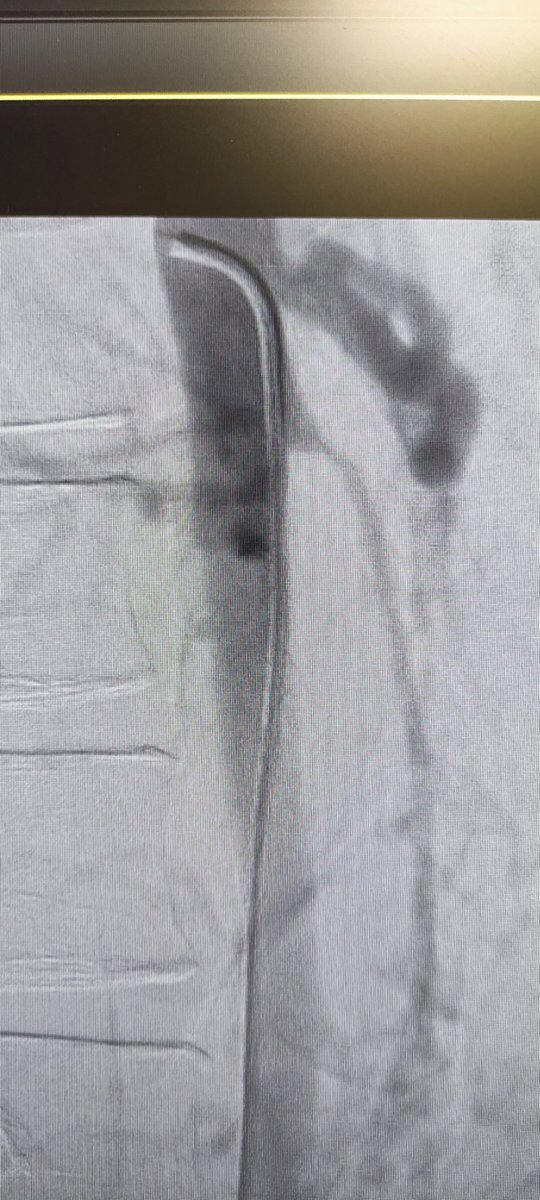

Superior mesenteric vein access for portal vein recanalization - Transjugular Intrahepatic Portosystemic Shunt in Chronic Portal Vein Thrombosis PAIRS PAIRS Society of Interventional Radiology CIRSE JVIR The Arab Journal of Interventional Radiology #irad #interventionalradiology #radiologia #mexico #tips